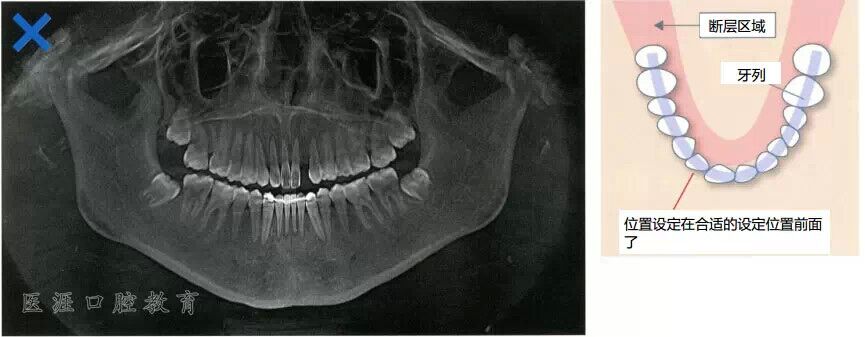

牙列往后方與斷層區(qū)錯開